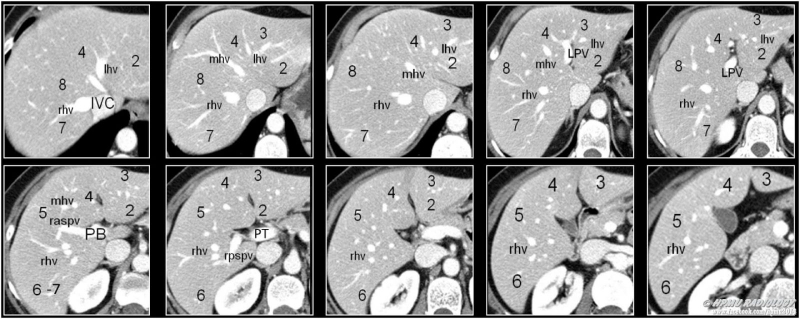

Phương pháp chụp CT ổ bụng còn có tên gọi khác là chụp cắt lớp ổ bụng, là phương pháp chụp cắt lớp vi tính. Đây là phương pháp đang ngày càng được sử dụng phổ biến trong y học và khoa học để chẩn đoán bệnh và nghiên cứu khoa học. Nếu như trước đây, phương pháp này chỉ áp dụng đối với việc chụp sọ não thì ngày nay nếu muốn tầm soát và kiểm tra thì có thể thực hiện ở hầu hết đối với các bộ phận trong cơ thể người và cả ổ bụng. Chỉ mất vài phút để chụp CT sử dụng tia X quang đi qua ổ bụng của người bệnh. Khi nhận được kết quả trên máy tính là những hình ảnh 2D hoặc 3D mặt cắt ngang ổ bụng. Phương pháp này giúp các bác sĩ chẩn đoán những bất thường và bệnh lý ở vùng bụng.

Dựa vào hình ảnh kết quả chụp CT ổ bụng giúp bác sĩ có thêm thông tin để chẩn đoán các nguyên nhân gây bệnh lý sau: Giúp bác sĩ có đủ thông tin để xác định nguyên nhân gây đau bụng. Từ kết quả này bác sĩ có thể loại trừ hoặc chẩn đoán bệnh lý ung thư các tạng trong ổ bụng như ung thư đại tràng, ung thư buồng trứng và ung thư biểu mô tế bào gan. Kiểm tra tình trạng chấn thương ổ bụng và mức độ nhiễm trùng và tình trạng của mật, gan, tụy cũng như phát hiện viêm bể thận, sỏi thận…